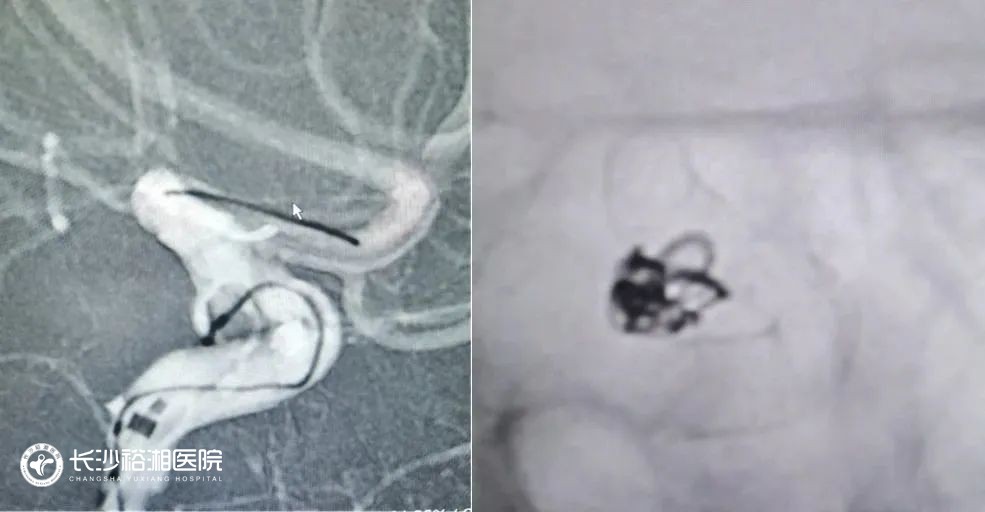

血管內(nèi)介入栓塞術(shù)無需開顱,通過人體血管天然通道實現(xiàn)對動脈瘤的治愈性栓塞,是一種安全有效的微創(chuàng)手術(shù)方法。隨著栓塞材料和治療理念的不斷進步,目前介入栓塞適用于絕大部分顱內(nèi)動脈瘤,尤其是巨大動脈瘤、夾層動脈瘤、頸眼動脈瘤、椎基底動脈瘤和血泡樣動脈瘤等復(fù)雜動脈瘤的治療。我院擁有省內(nèi)先進的腦血管病復(fù)合手術(shù)室,神經(jīng)外科腦血管病治療團隊具有熟練扎實的手術(shù)技巧,在復(fù)雜顱內(nèi)動脈瘤的介入栓塞和外科治療方面經(jīng)驗豐富。

(腦血管造影檢查)

(血流導(dǎo)向裝置置入)